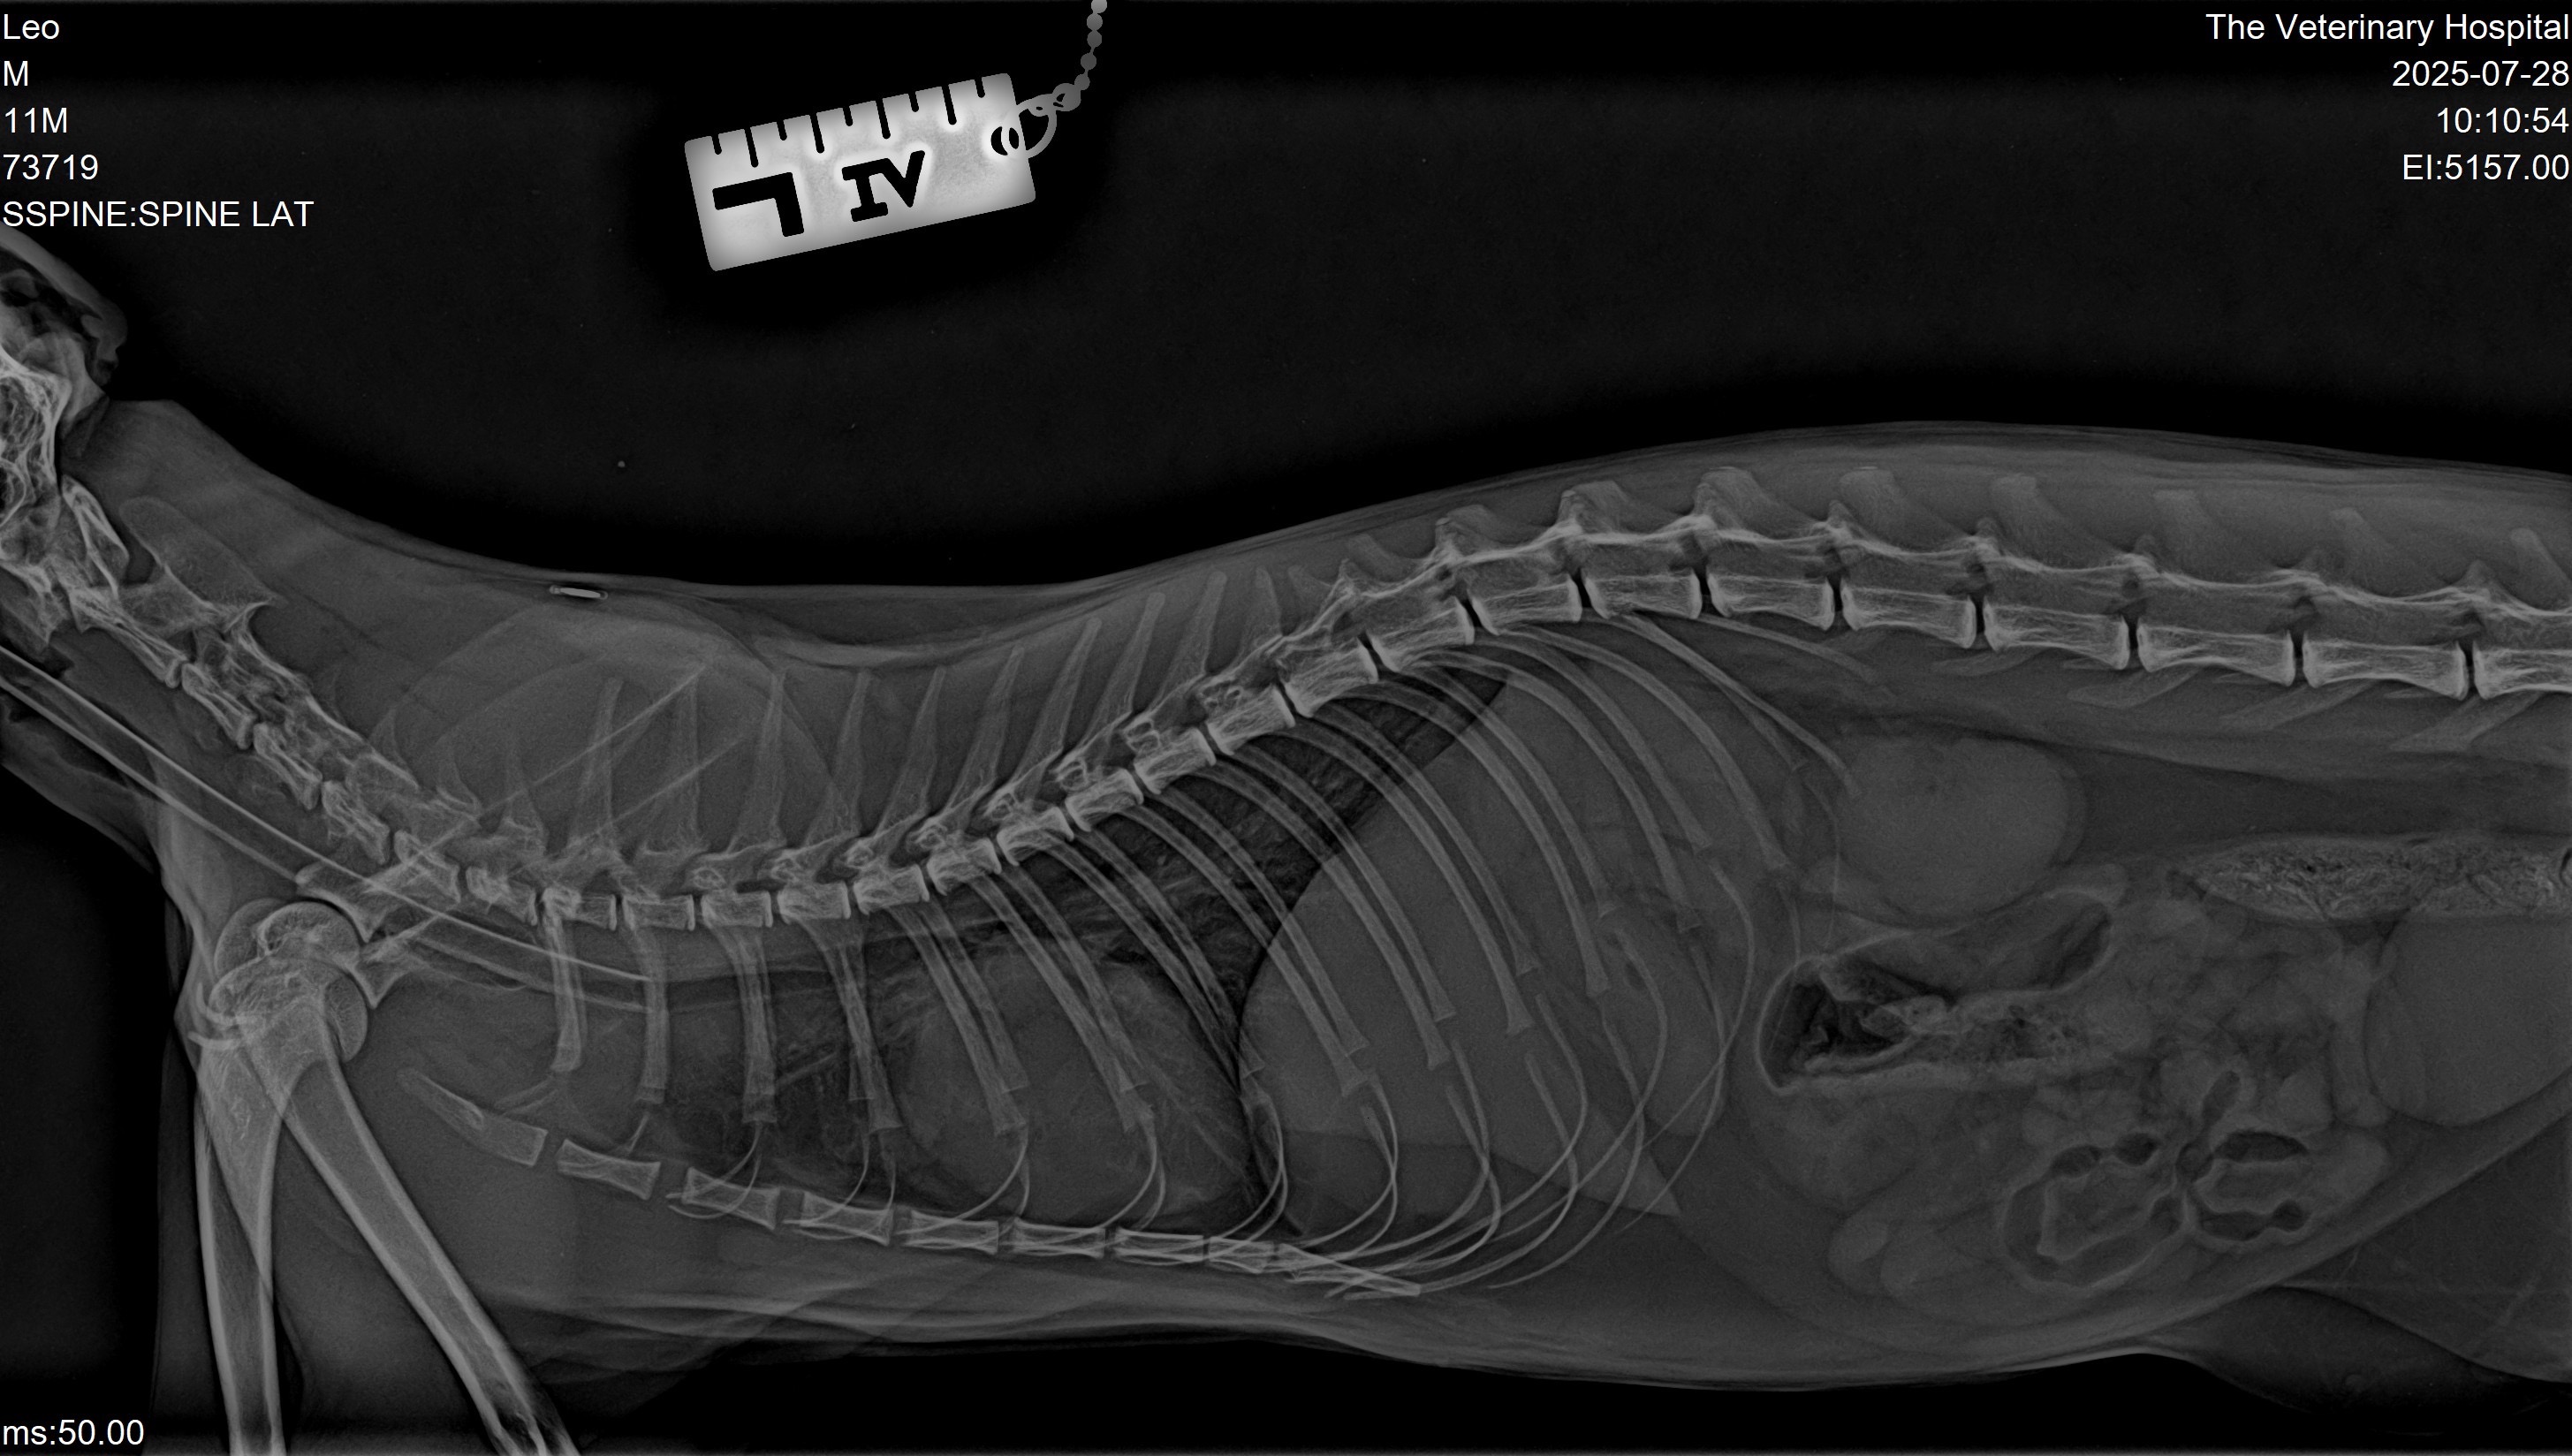

This sweet, brave boy suddenly collapsed without warning. He’s already been seen by three different vets, but none have been able to find the cause/solution of his condition. Now, Leo’s mobility is rapidly deteriorating — and we are running out of time.

Leo is currently hospitalised at The Veterinary Hospital, under the care of a senior Orthopaedic and Spinal Surgeon. But to have a real chance at recovery, he urgently needs a CT scan and MRI to uncover what’s happening and prevent permanent paralysis.